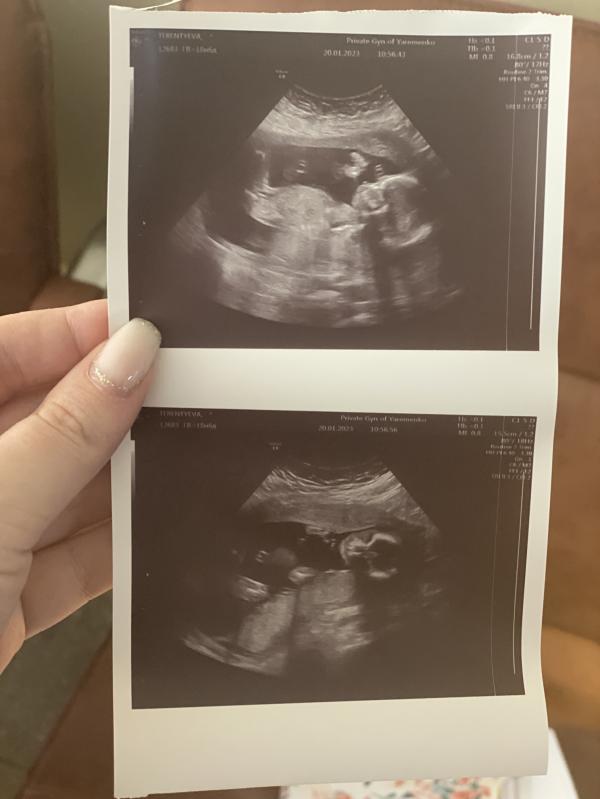

Сходили на второй скрининг и это просто умиление 🥰

3д как планировали не получилось, конечно же нужно было в этот момент руками закрыть лицо 😂

Вообщем я официально добавляю себя в список тех, у кого Ярёменко сразу предположил и потом подтвердил пол 😍

Еле ловили для фото и замеров 🫣